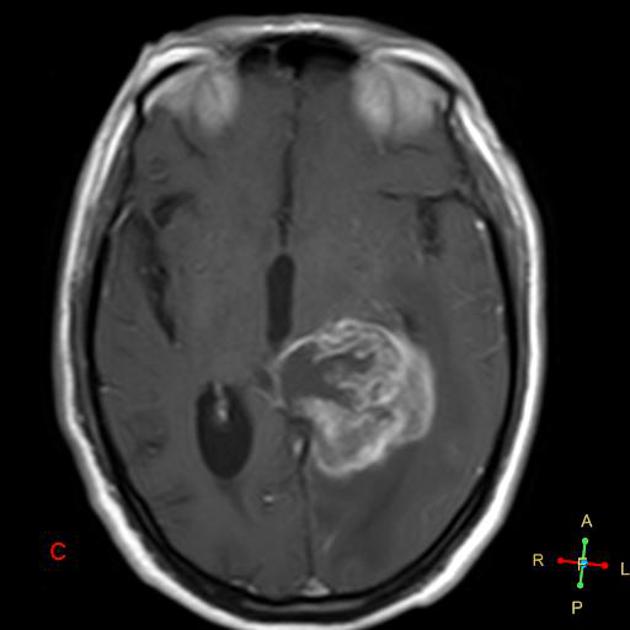

AA T1 with gad

GBM T1 with gad

Radiotherapy General Fields

The treatment fields for HGG in pediatrics, similar to adults is the imaging enhanced region plus a margin. The initial GTV is the MRI T2 abnormality (edema). The initial CTV = GTV + 1.5 cm, corrected for anatomical barriers. The usual dose to this volume is 50.4 - 54 Gy at 1.8 Gy/fraction. The second GTV (boost GTV) is the T1+gadolinium enhancement. The second CTV=GTV+1 cm. This is then carried to 59.4 Gy.

• The final GTV = T1+ gad image

• The final CTV = GTV (final) + 1 cm margin (⇒ to 59.4 Gy)